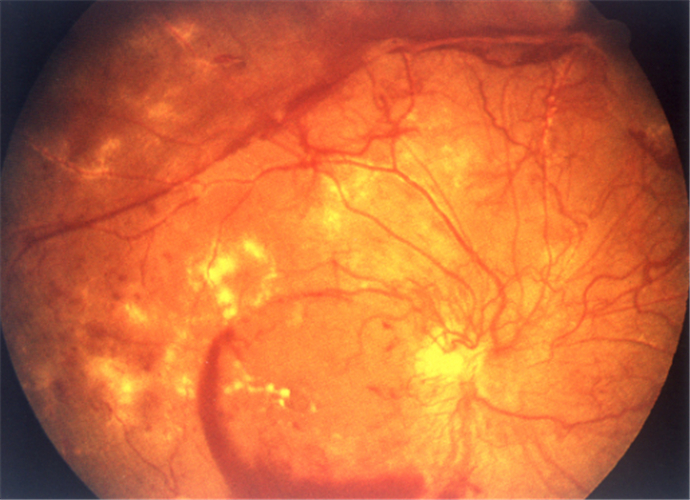

增值引發視網膜脫落

增值併發視網膜脫落